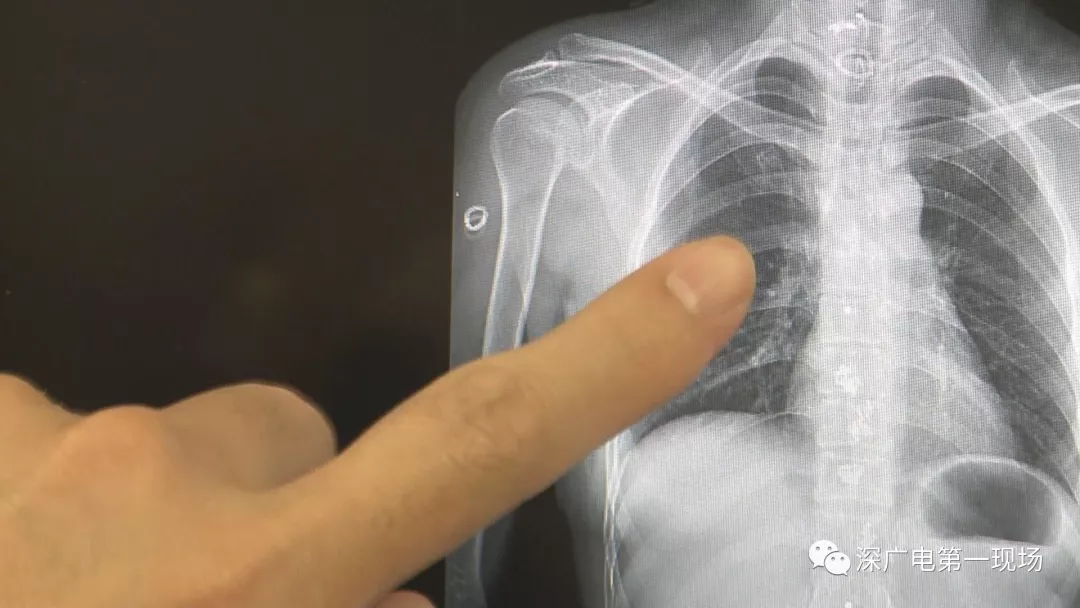

深圳一女子全身被植入彈簧圈,數(shù)量多到驚人!竟是為治這病…

“癲癇”本是一種神經(jīng)系統(tǒng)疾病

深大總醫(yī)院接診了一位癲癇病患者

經(jīng)醫(yī)院常規(guī)檢查后發(fā)現(xiàn)

為了治病

這位病人竟然在全身

被植入了大!量!彈!簧!

數(shù)量多到無(wú)!法!計(jì)!數(shù)!